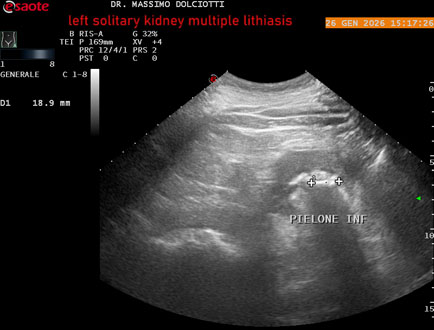

Data inserimento: 29/01/2026

Ecografia del: 26/01/2025

Strumento: Esaote MyLab Eight

Sonda: Conevx Multifrequenza 1-8 MHz

Età Paziente: M 78 anni

Motivazione dell'esame: follow up di litiasi al rene sinistro, in paziente sottoposto a nefrectomia destra.

Commento all'esame: le immagini ed il video documentano il rene sinistro in sede, di ecostruttura disomogenea per evidenza di multiple formazioni litiasiche al pielone superiore, delle dimensioni di 15,9 mm, al pielone medio di 17,5 mm e al pielone inferiore di 18,9 mm e morfovolumetria normale, con diametro bipolare di 115 (v.n. 90-120 mm) x 54 mm e parenchima renale dello spessore di 17 mm ( v.n. > 13 mm).

Conclusioni: litiasi multipla del monorene sinistro (multiple lithiasis of the left solitary kidney).

In collaborazione: Dr.ssa Marica Manfredi - Ancona, Dr. Ilir Qose - Ancona

Presentazione: Dr. Massimo Dolciotti - Ancona

Elaborazione digitale: Andrea Dini - Ancona